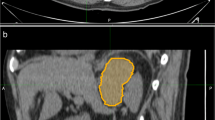

This retrospective study enrolled 178 patients with cancer history from three medical centres categorised as those with adrenal lipid-poor benign lesions or metastases. Patients were divided into training, validation, and external testing cohorts. Radiomics features were extracted from triphasic CT images (unenhanced, arterial, and venous) to establish three single-phase models and one triphasic radiomics model using logistic regression. Unenhanced and triphasic nomograms were established by incorporating significant clinico-radiological factors and radscores. The models were evaluated by the receiver operating characteristic curve, Delong’s test, calibration curve, and decision curve.

- ROI:

Region of interest